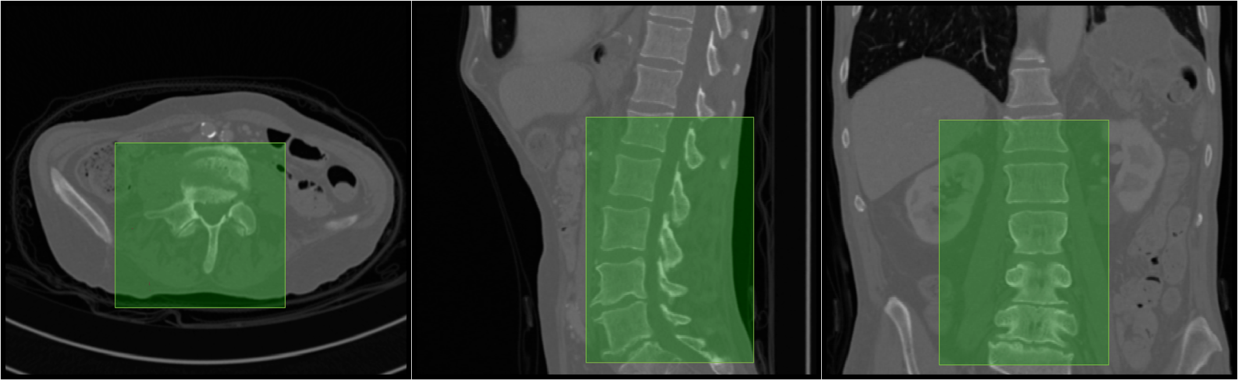

Each pass through the regressor using a feature corresponding to a certain voxel predicts the locations of the bounding planes with respect to that voxel. In order to speed-up the feature generation procedure without loss of useful information, only the significant voxels are considered for feature extraction. For this purpose, the voxels from the response of a Canny’s edge detector are used for feature extraction. Thus, every significant voxel votes for a prospective bounding box of which the most representative bounding box is chosen. Figure 2 shows a few examples of the localised lumbar regions.

Figure 2: Lumbar Localisation: The axial, sagittal, and coronal views of the bounding box localising the lumbar section. (Row 1) Case 18 containing severe abnormalities such as multiple fractures and scoliosis is localised perfectly. (Row 2) Case 22 shows a mild under-localisation, not localising a top region of L1.

To measure the performance of localisation, a measure of sensitivity (or true positive rate) was used, as defined: S=1|𝒢c||𝒢|,𝑆1𝒢superscript𝑐𝒢S=1-\frac{|\mathcal{G}\cap\mathcal{B}^{c}|}{\mathcal{|G|}}, where 𝒢𝒢\mathcal{G} is the of set voxels in the ground truth segmentation, and \mathcal{B} is the set of voxels within the bounding box. We use the ground truth segmentation for Rater-1 for this purpose. The sensitivity measures on the test set are shown in table 1, with a few cases shown visually in figure 2. We obtain a near perfect localisation of 1.0 in all cases except one (Case025). In order to completely cover the lumbar region, a tolerance of 15 voxels is added to the bounding boxes on all sides before considering the localisation for for the next stage.